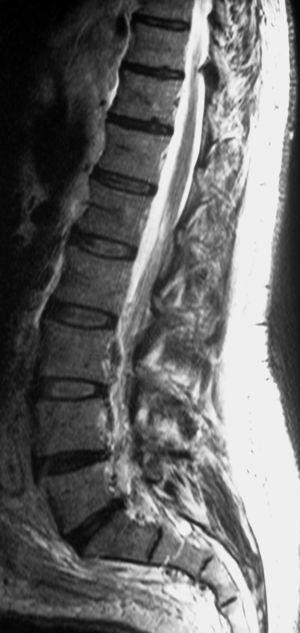

Se realizó una resonancia magnética (RM) de la columna lumbar (sin y tras contraste intravenoso) y se observaron, además de la masa retroperitoneal que comprimía la VCI, unas imágenes puntiformes y lineales hipointensas en todas las secuencias que ocupaban el espacio epidural adyacente al muro posterior de las vértebras lumbosacras, que se extendían a través de los agujeros de conjunción hacia las partes blandas perivertebrales (figs. 1-3). Esta alteración correspondía a estructuras vasculares dilatadas dependientes del plexo venoso epidural vertebral.

Fig. 2. Resonancia magnética ponderada en T2 (A) sagital línea media y (B) parasagital. En el espacio epidural anterior (A) y en los forámenes de conjunción (B) se aprecian estructuras vasculares con aspecto serpinginoso y arrosariado (flechas).